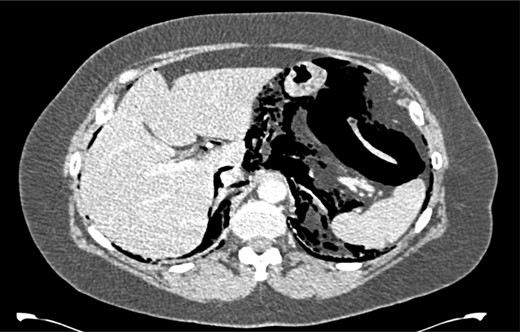

After her procedure she complained of swelling in her neck. This was not accompanied by shortness of breath, chest pain or abdominal pain. On examination, her oxygen saturation was 99% on room air, with normal respiratory and heart rate. Her respiratory examination was normal and her abdomen was soft and non-tender. She had marked crepitus over her clavicles, supraclavicular fossa and most of her neck. Her erect chest X-ray revealed air under both hemidiaphragms and significant pneumomediastinum (Fig. 1). A computed tomography (CT) scan of her chest, abdomen and pelvis was requested. This CT-scan revealed very extensive spreading of surgical emphysema in the retroperitoneum, extending into the mediastinum with small volumes of free intraperitoneal gas (Figs 2–4).

CT scan of abdomen showing free intraperitoneal gas compressing the splenic flexure.